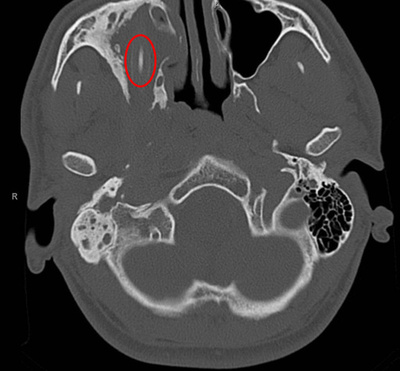

医師らは当初、全身スキャナーによる検査で体内に大きな固形物が見つかったことから、腫瘍だと考えた。しかし検査を進めるにつれ、数十本もの折り畳みナイフが見つかった。開くと最大で全長18センチのナイフまで含まれていたという。

執刀医の一人はAFPに対し、「直ちに手術の準備を行い、刃物を摘出した。中には開いた状態のナイフもいくつかあり、出血していた」と明かした。